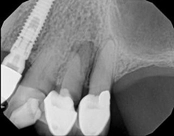

Lower molar failed root canal, microsurgery saved the tooth:

Before

Immediately after

3-month follow-up with complete healingThis patient presented with a failed root canal. The root canal became infected. An apicoectomy (apical microsurgery) was performed using the laser. Patient had minimal swelling, minimal discomfort, and fast healing. The tooth was saved and an implant avoided. This tooth tends to have a lower success rate with root canal therapy; thankfully apical microsurgery was available to save the tooth.

At the 3 month follow-up, the gums look like nothing was done thanks to the skill and use of the laser for the procedure.